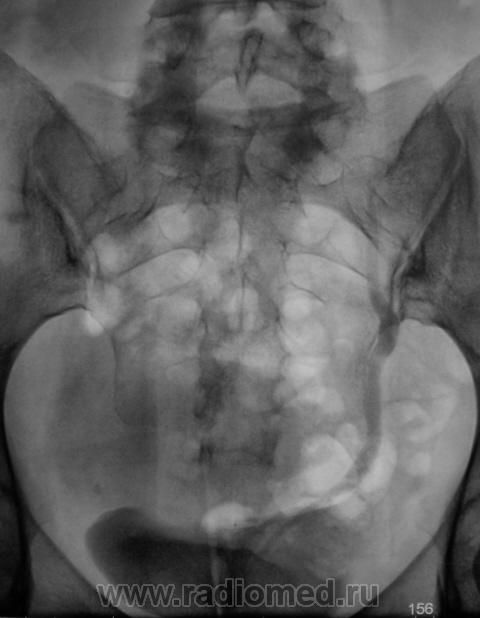

Почки контурируются в типичном месте, обычной формы и размеры. R-позитивных уроконкрементов в проекции мочевыносящих путей на обзорной урограмме не выявлено. ЧЛС контрастированы синхронно, не расширены. Мочеточники контрастированы, левый просматривается на всем протяжении, в нижней 1/3 незначительно стойко расширен, оттеснен кверху и вправо (хотя возможен такой вариант расположения устьев мочеточников - к сожалению правый мочеточник не визуализируется т.е. несчем сравнить). В мочевом пузыре, слева от срединной линии, дефект наполнения с четкой неровной границей.

Не хватает клинических данных (хотя бы укажите с какой стороны болит?) и других изображений контрастированного мочевого пузыря (необходимо выяснить стойкий это дефект наполнения или нет).

Валентин Львович! Дефект наполнения мочевого пузыря слева имеется. Сказать вне пузырный или внутрипузырный сложно. Я бы выполнил УЗИ мочевого пузыря. Урологам порекомендовал бы цистоскопию.

Боли больше слева. Мне этот чертов дефект наполнения в мочевом пузыре тоже "не давал покоя".

У женщин часто так матка поддавливает мочевой пузырь

Мы решили сразу после исследования сделать томографию мочевого пузыря.

Меня немного смутило сужение мочеточника у левой почки, возможно перистальтика. Прошу обратить внимание.